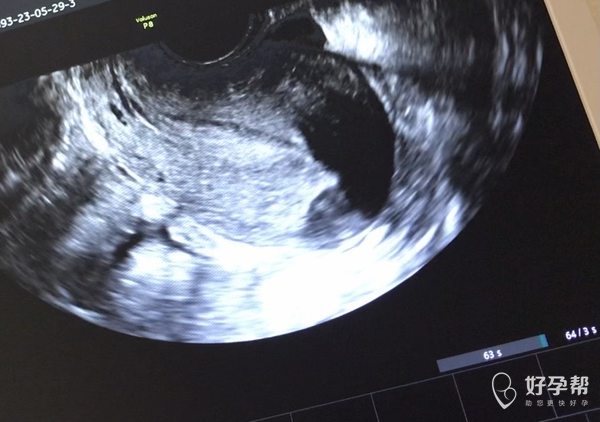

月经期查b超见图片是否提示输卵管积水还有什么

B超要图片和报告结合看,超声医生最清楚,这样留下的固定图片不能反应真实情况目前图片反应的是有盆腔积液,子宫未见异常,输卵管积液不好说,超声留的切面不好确定